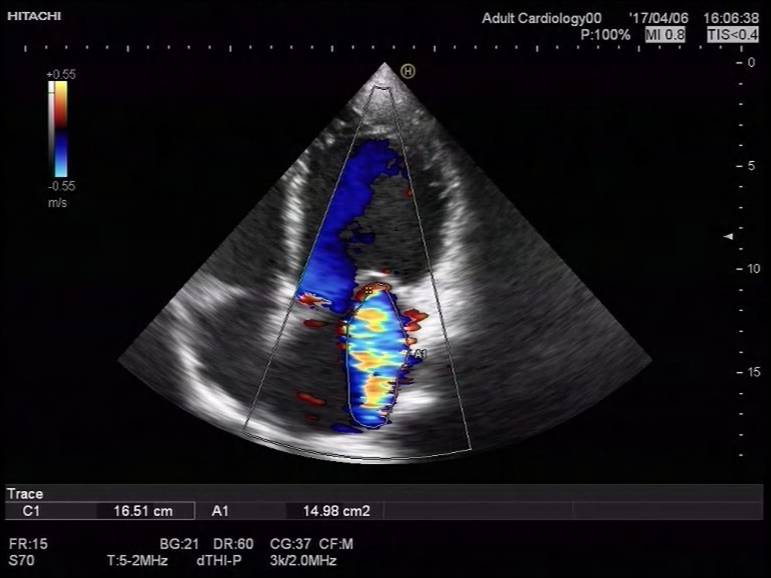

2017-4-7心超检查报告:

符合扩张型心肌病声像图改变:

◆1、左室壁运动弥漫性减弱 左心及右房大 ,EF 21%,左室缩末内径 76mm,舒末内径85mm。

◆ 2、二尖瓣前瓣瓣尖轻微对合错位并二尖瓣重度关闭不全(瓣环扩张所致)

◆3、 三尖瓣中度反流、主动脉瓣微量反流 左室收缩舒张功能减退 肺动脉高压(中度)